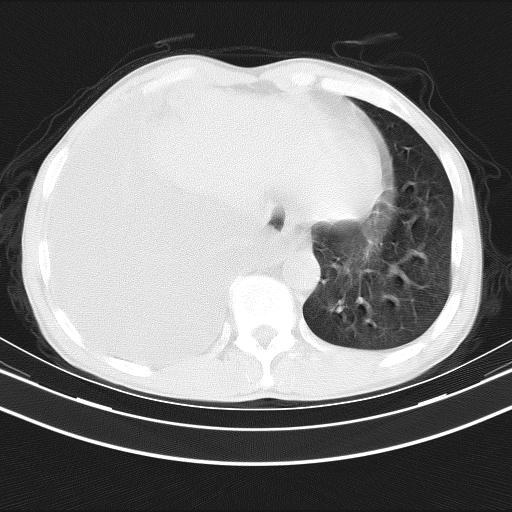

男性,44岁,结核病史多年。现胸闷气短,咳嗽,偶咳血。

1)两肺继发性肺结核伴空洞形成,左肺多发性结核球。2)右侧大量胸腔积液伴右肺部分膨胀不全。3)纵隔淋巴结肿大。

1,双肺多发结节 并空洞影改变, 左侧胸腔积液并部分包裹, 结合原病史首先考虑结核. 但也不除外其它.

2,左侧有一根肋骨陈旧性骨折? 建议追查 .

吉大一院胸水抽检结果:结核性胸水